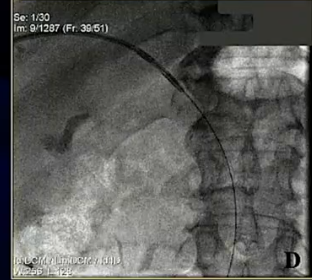

病例2 60岁 男性 肝癌合并门静脉癌栓

F:随访CT图像(术后5.5个月)患者未接受任何其他治疗。左叶肿瘤缩小和未治疗的左门静脉再通(白色箭头)清楚地记录了PV肿瘤血栓RF处理的远端效应